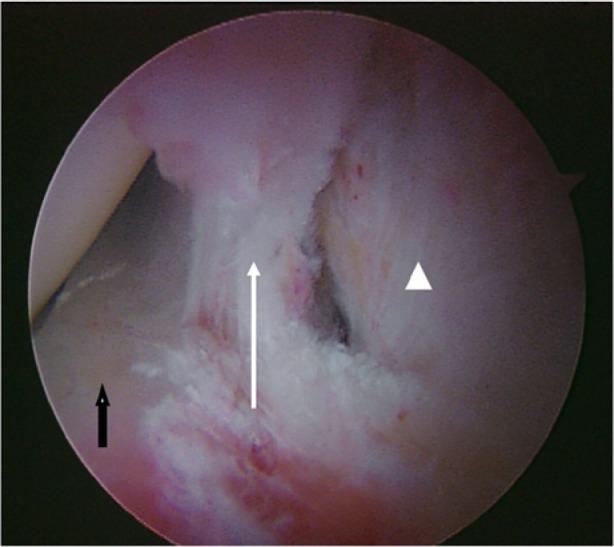

Increased stresses across the bony hemipelvis result when athletes with FAI attempt to achieve supraphysiologic, terminal ranges of motion (ROM) through the hip joint required for athletic competition. This can manifest as pain within the pubic joint (osteitis pubis), sacroiliac joint, and lumbosacral spine. Subclinical posterior hip instability may result when attempts to increase hip flexion and internal rotation are not compensated for by increased motion through the hemipelvis. Prominence of the anterior inferior iliac spine (AIIS) at the level of the acetabular rim can result in impingement of the anterior hip joint capsule or iliocapsularis muscle origin against the femoral head-neck junction, resulting in a distinct form of mechanical hip impingement (AIIS subspine impingement). Iliopsoas impingement (IPI) has also been described as an etiology for anterior hip pain. IPI results in a typical 3-o'clock labral tear as well as an inflamed capsule in close proximity to the overlying iliopsoas tendon. Injury in athletic pubalgia occurs during high-energy twisting activities in which abnormal hip ROM and resultant pelvic motion lead to shearing across the pubic symphysis.